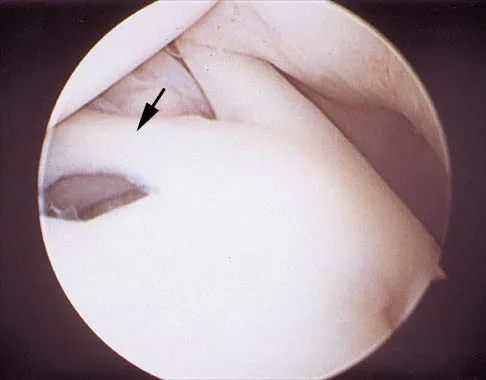

A 24-year-old athlete has a painful right shoulder. Figure 30 shows an intra-articular photograph that was obtained through a posterior portal during arthroscopy; the labrum is indicated by the arrow. Based on these findings, management should consist of

Explanation